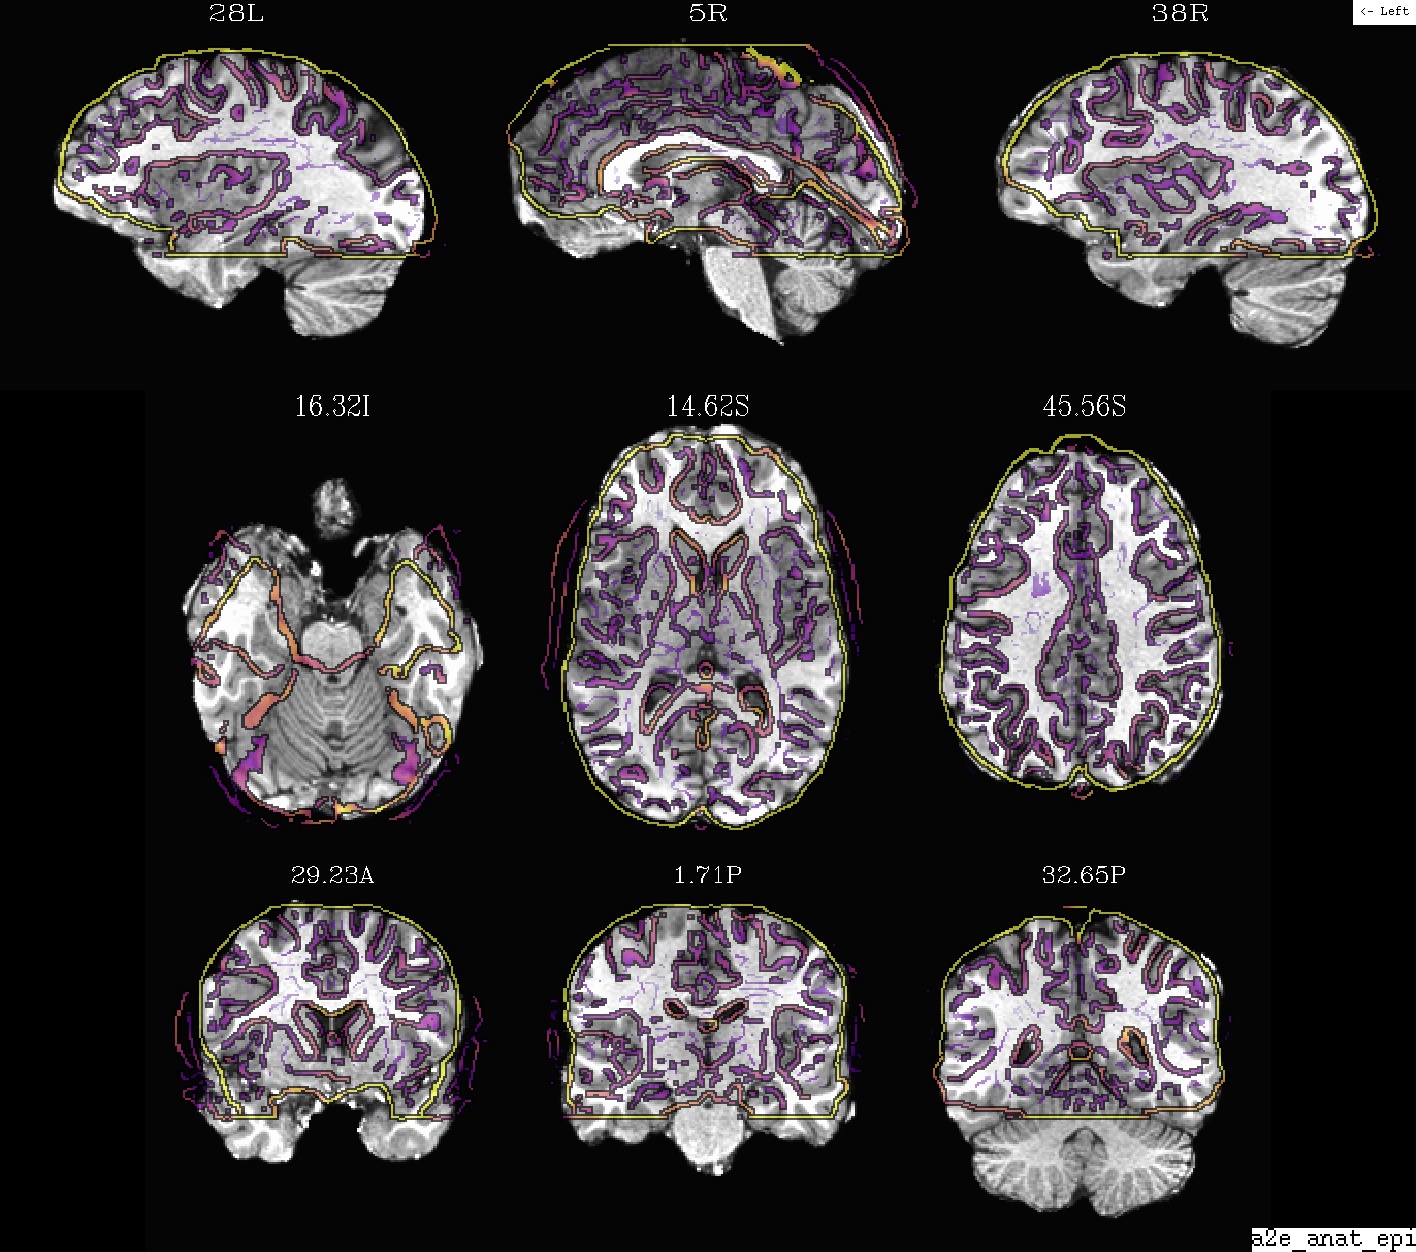

Ex. 0: Anatomical + EPI alignment (in final template space)¶

A display of how the anatomical and an EPI volume overlay after alignment. The dsets are shown after their warping to standard space.

The anatomical is the underlay (setting the grid resolution), and the olay is “edge-ified”.